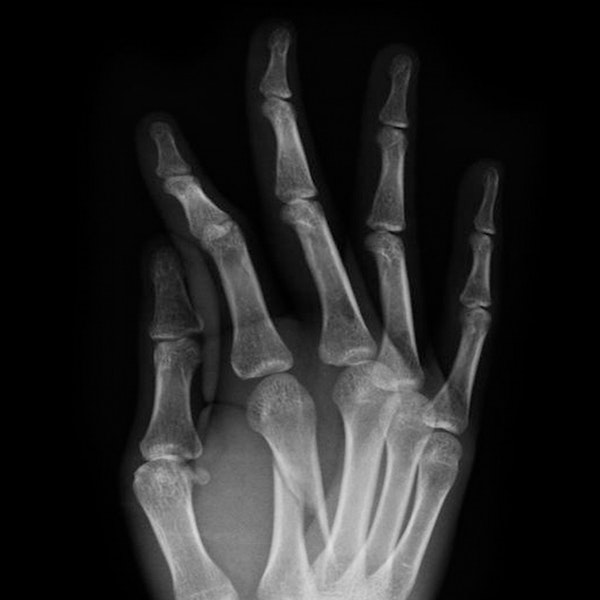

Dr. Vagner specializes in treating issues in the elbow, wrist, and hand. The hand is a remarkably complex system of nerves, tendons, ligaments, and bones, and our surgeon has spent his career studying its intricacies.How does the hand work?

The bones in the hand can break easily due to any number of factors, such as a bad fall, a car accident, or contact sports. If you injured your hand and are experiencing pain and swelling, one of your bones may be fractured and you should seek the attention of an orthopedic physician. If you wait too long to have your hand professionally examined, the bones may heal incorrectly, which can cause long-lasting pain and impaired functionality.

Dr. Vagner is able to diagnose and treat both mild and severe hand fractures at his practices in the Austin, TX, area. He is usually able to set the bone and provide a cast or splint without the need for surgery. In the case of advanced fractures that require surgery, Dr. Vagner uses safe and modern tools and techniques to conservatively repair the hand.